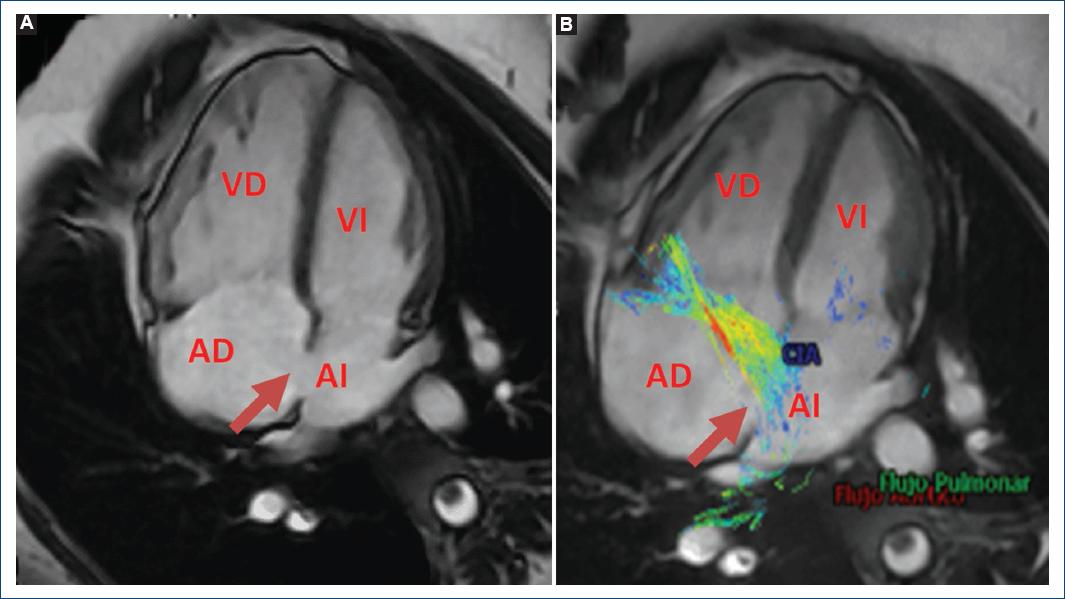

En el ejemplo 1 se muestra el estudio de un paciente con comunicación interauricular ostium secundum que es el más frecuente (70% de todas las comunicaciones interauriculares). Se presenta en la zona central del tabique auricular, lo que tiene como consecuencia de forma inicial un cortocircuito izquierda-derecha, también conocido como «derivación», a través de la comunicación interauricular, lo que condiciona una sobrecarga de volumen en las cavidades cardiacas derechas e hiperflujo pulmonar, pudiendo cursar con hipertensión pulmonar, arritmias auriculares e insuficiencia cardiaca9,10. En este caso, en las secuencias de flujo 4D fue posible ubicarnos directamente sobre el defecto interauricular de forma perpendicular sobre el flujo de comunicación interauricular, permitiendo analizar su localización y morfología a nivel del septo interauricular, llevar a cabo las mediciones necesarias (diámetros y área) en la fase del ciclo cardiaco y, ciertamente, la medición directa del flujo (Fig. 1). Así mismo, mediante software de análisis avanzado fue ejecutable la activación de vectores y uso de streamlines y pathlines que nos permitieron identificar claramente de forma visual la dirección del flujo, tan importante en este tipo de patología cardiaca. Al mismo tiempo, la secuencia de flujo 4D nos permitió la cuantificación del Qp:Qs, el flujo sistémico (Qs) y el flujo pulmonar (Qp) en cualquier nivel deseado; de esta forma es posible una excelente valoración interna de las diversas mediciones que llevan a una mayor congruencia del análisis y los posteriores resultados (Fig. 2).